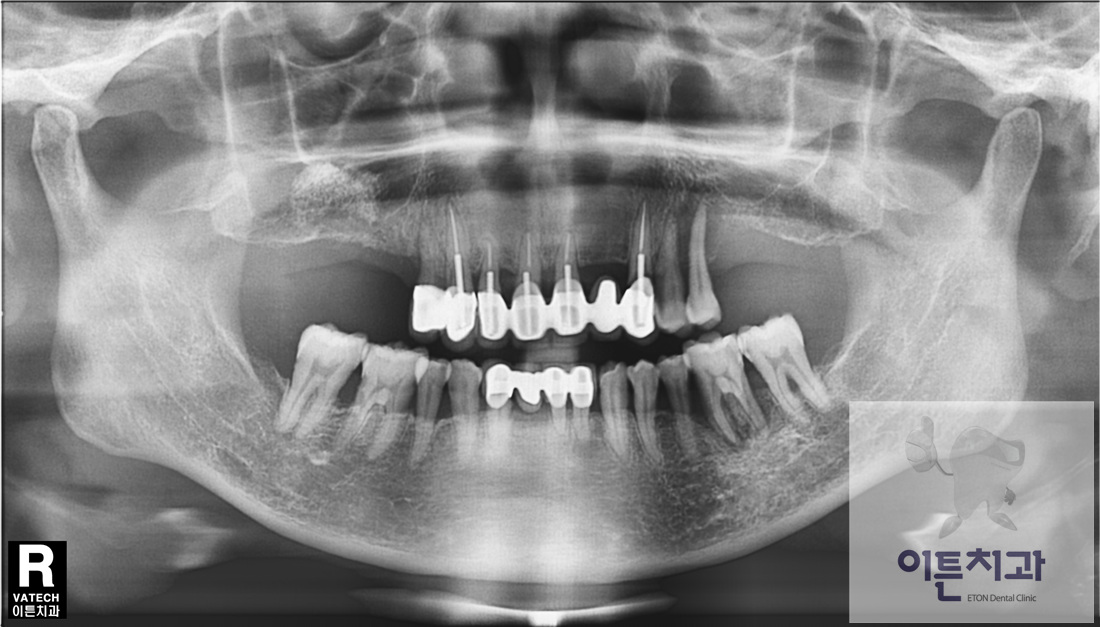

´Ù¼ö Ä¡¾Æ ÀÓÇöõÆ® ¼öº¹

50´ë ¿©¼º ȯÀÚºÐÀ¸·Î¼ »ó¾Çµ¿ °ñ À̽ļú, Ä¡Á¶Á¦ Áõ°¼ú µîÀÇ °ñÀ̽ļúÀ» ÅëÇØ Ä¡Á¶Á¦¸¦ Àç°ÇÇϰí ÀÓÇöõÆ®¸¦ ½Ä¸³ÇÏ¿© »ó½ÇµÈ Ä¡¾ÆµéÀ» ¼öº¹ÇÑ Áõ·ÊÀÔ´Ï´Ù.